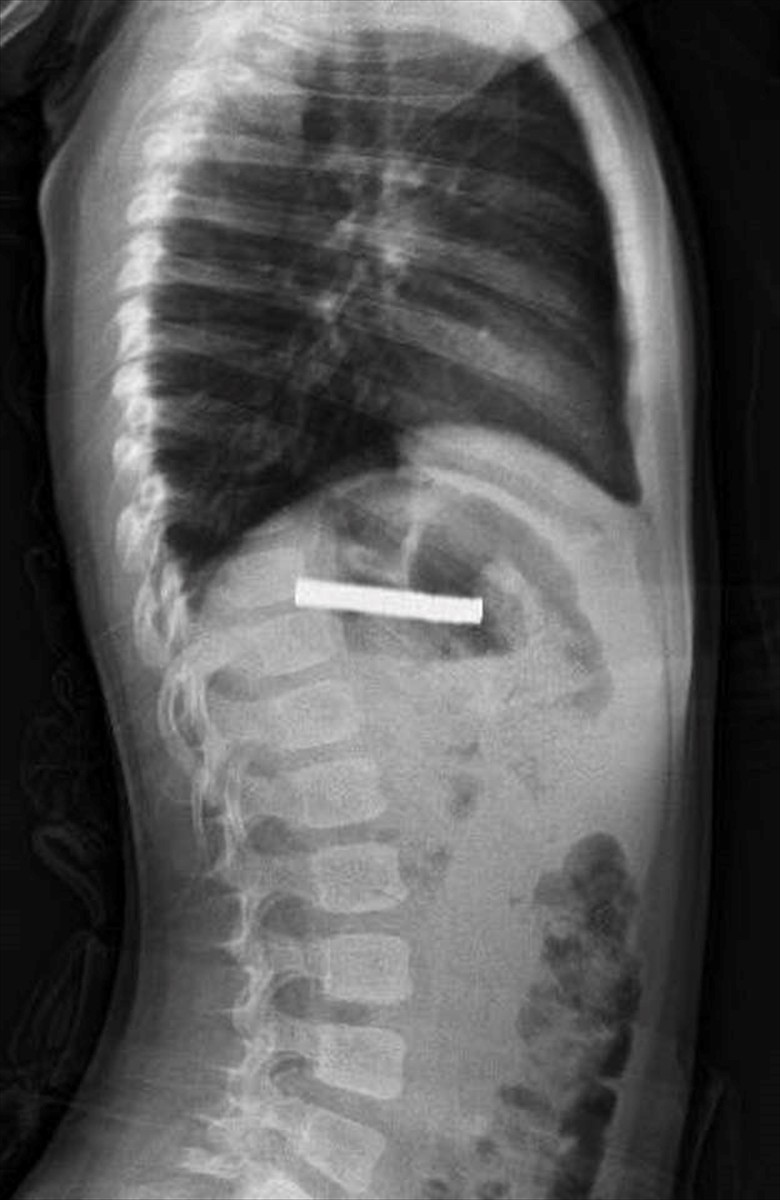

Erzurum'da evde oyun oynarken bulduğu 19 mıknatısı yutan 3 yaşındaki çocuk, rahatsızlanması üzerine ambulansla Erzurum Şehir Hastanesi'ne kaldırıldı. Yapılan tetkiklerin ardından hasta, acil durum nedeniyle ambulans helikopter ile Fırat Üniversitesi (FÜ) Hastanesi'ne sevk edildi.

FÜ Çocuk Gastroenteroloji Hepatoloji ve Beslenme Bilim Dalı Başkanı Prof. Dr. Yaşar Doğan ve ekibinin tetkiklerinde mıknatısların birbirine yapışarak çocuğun yemek borusunu tıkadığı tespit edildi. Müdahale sırasında mıknatıslar yemek borusundan mideye alınarak, mideden özel bir file ile çıkarıldı. İşlem başarılı geçti.

Elazığ'da 3 yaşındaki çocuğun yuttuğu ve yemek borusunu tıkayan 19 mıknatıs, Fırat Üniversitesi Hastanesi'nde yapılan başarılı bir operasyonla çıkarıldı.